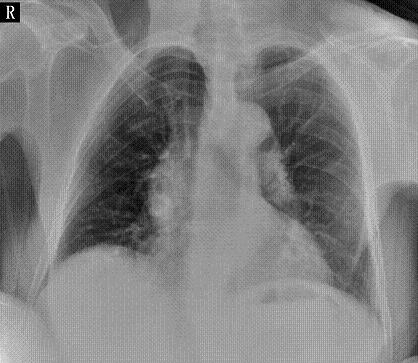

标题: X6742:女,64岁,双侧胸痛,咳嗽,驼背 [打印本页]

肺纹理增多,主动脉主动脉硬化,下肺气管感染?

支气管炎,轻度肺气肿。

主动脉型心影,升降主动脉增宽迂曲,右心缘里那类圆形高密度影要关注一下。

支气管炎,右侧轻度肺气肿,双肺门钙化灶,主动脉型心影,脊柱侧弯畸形。

双肺门多发钙化?主动脉迂曲。

双肺纹理增重,肋间隙变窄(可能为驼背所致),余未见明显异常。

两肺纹增粗,胸主动脉扩张迂曲。必要时ct检查。

主动脉迂曲、扩张,建议行ct进一步检查,排除主动脉夹层

驼背造成主动脉增宽迂曲明显,正如黑白光影版主所说布纹影太重,干扰肺野观察。